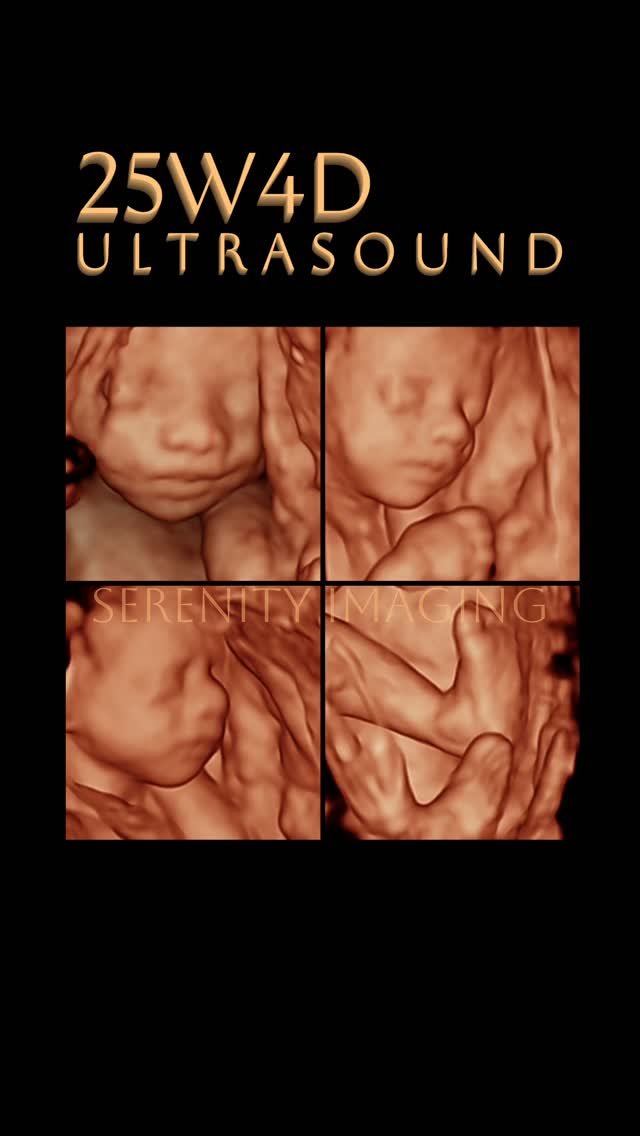

3D/4D/5D baby ultrasound service. We are revolutionizing the way expecting parents can bond with their little ones even before they are born. These advanced ultrasound technologies provide a vivid and lifelike representation of the baby in the womb, capturing charming details that previously remained unseen.

With elective 3D ultrasounds, parents can now see the contours of their baby's face, tiny fingers, and delicate features with astonishing clarity.

The extra dimension of 4D ultrasound adds movement to the equation, allowing parents to witness their baby's yawns, kicks, and even smiles in real-time.

Our 5D ultrasound service includes an enhanced HD live ultrasound, enhanced videos, and high-resolution images of your baby.